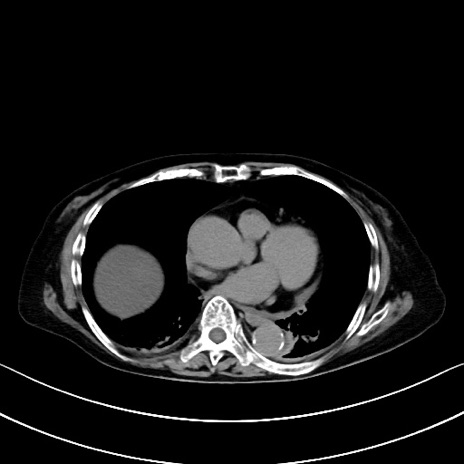

症例40(横断像)他院1日前

横断像

他院CT